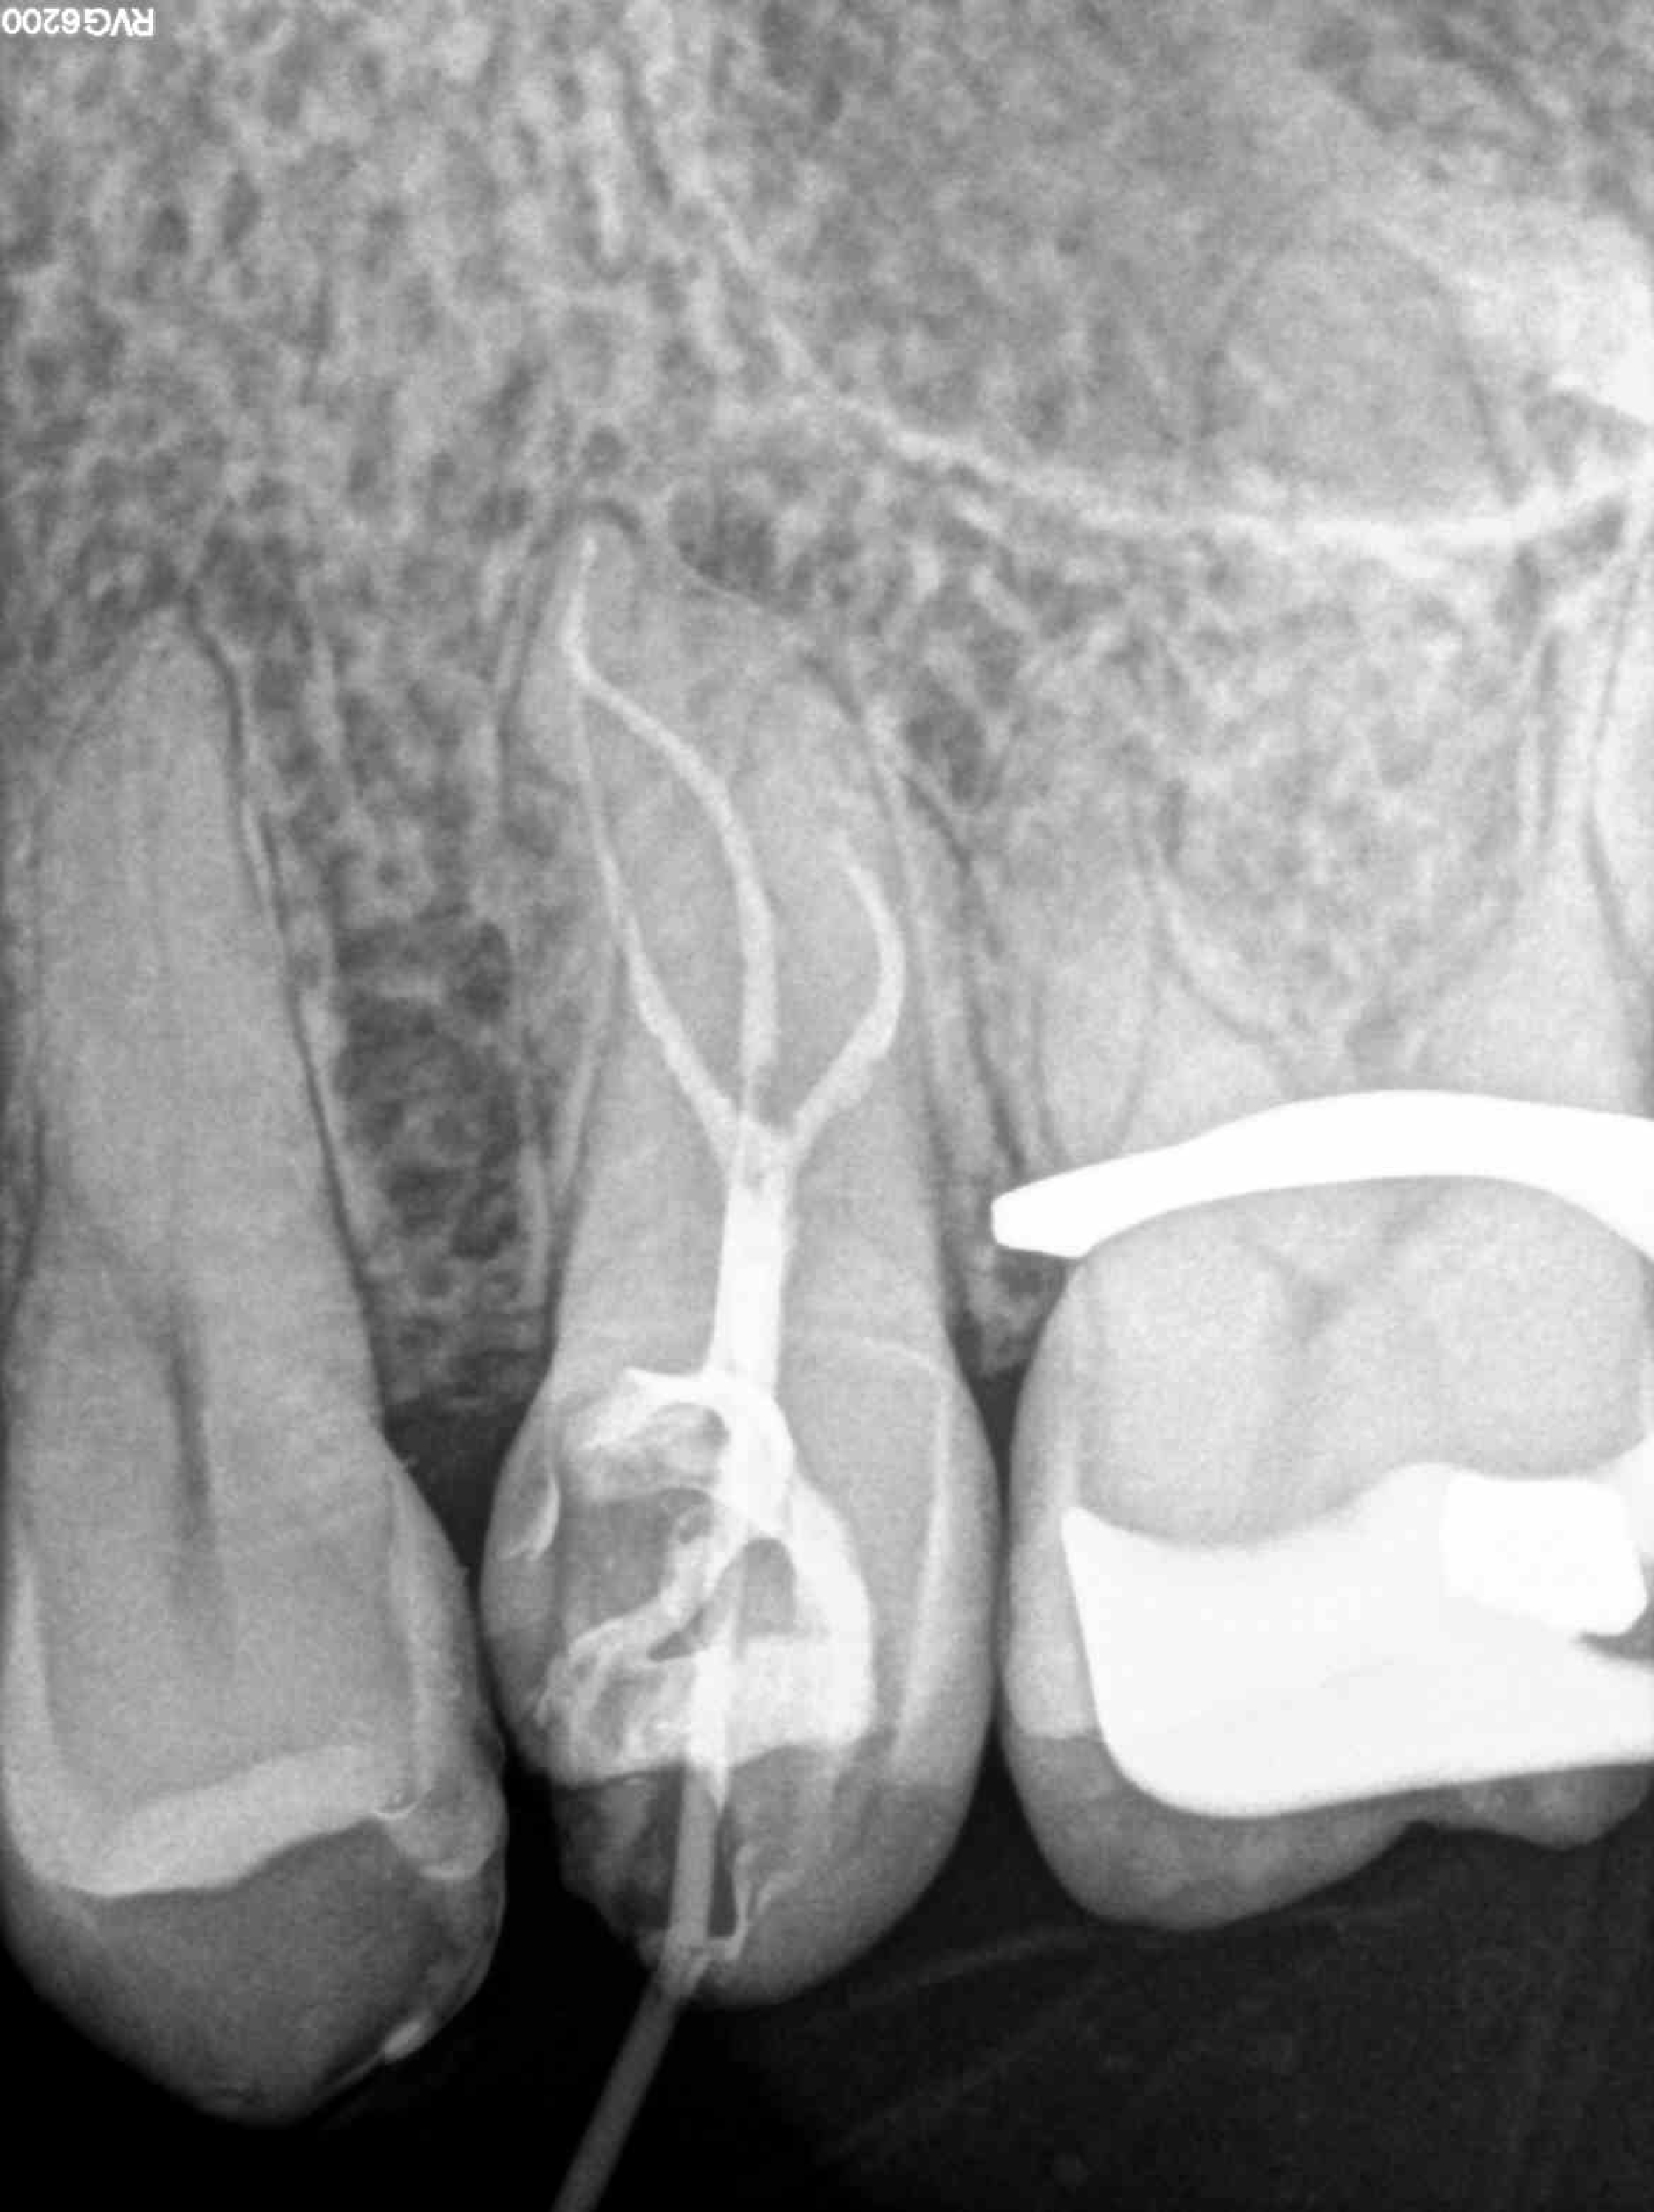

* Haz click sobre las radiografías para verlas a mayor tamaño

Haz click sobre las radiografías para verlas a mayor tamaño